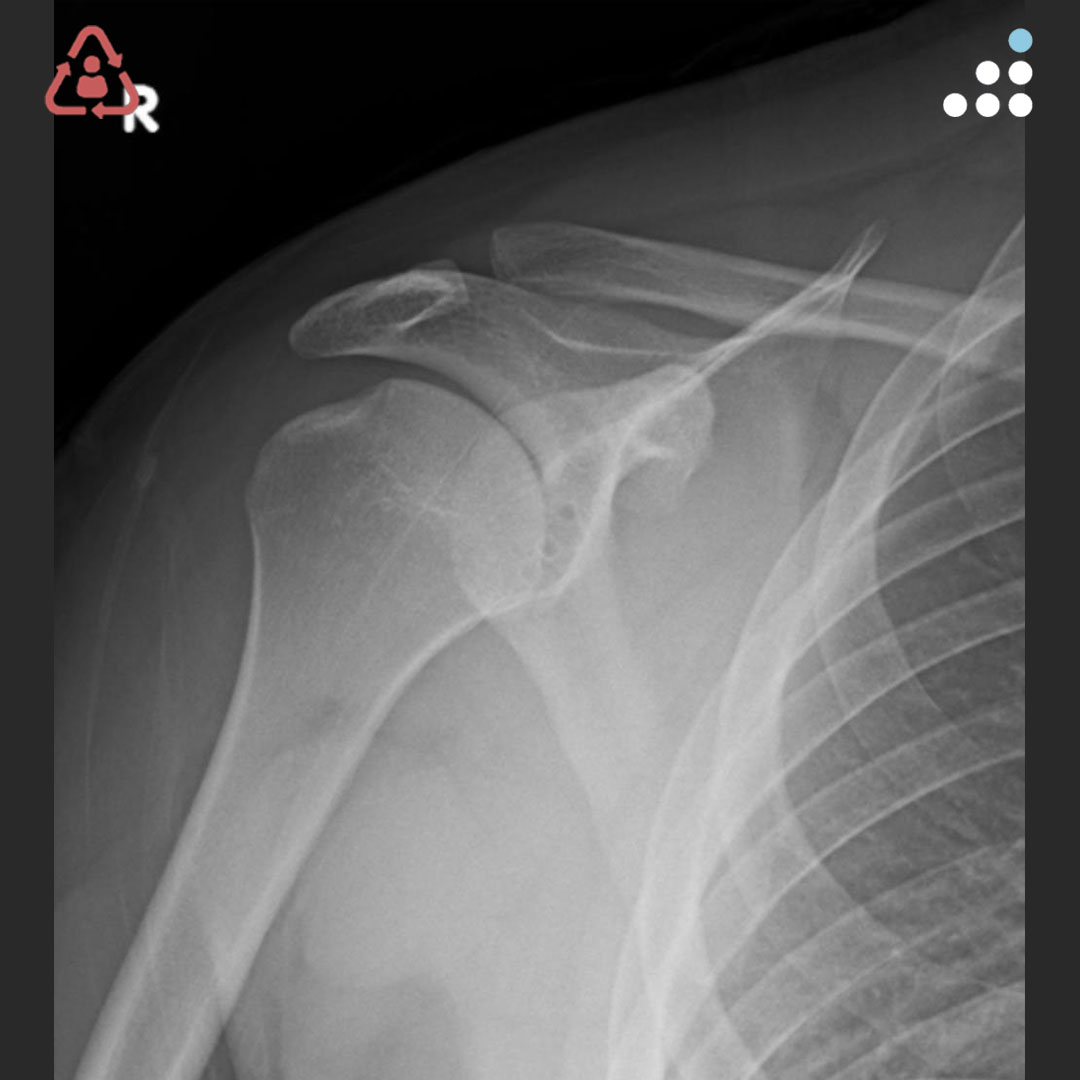

@DrBryanSaltzman @orthotraumamd @orthobullets @VaniSabesanMD @JSanchezSotelo @RachelFrankMD @MarkFrankleMD @shoulderMD I agree with Dr Saltzman. This is a preservable joint in a young active individual. Tuberoplasty or spacer would be my choice.